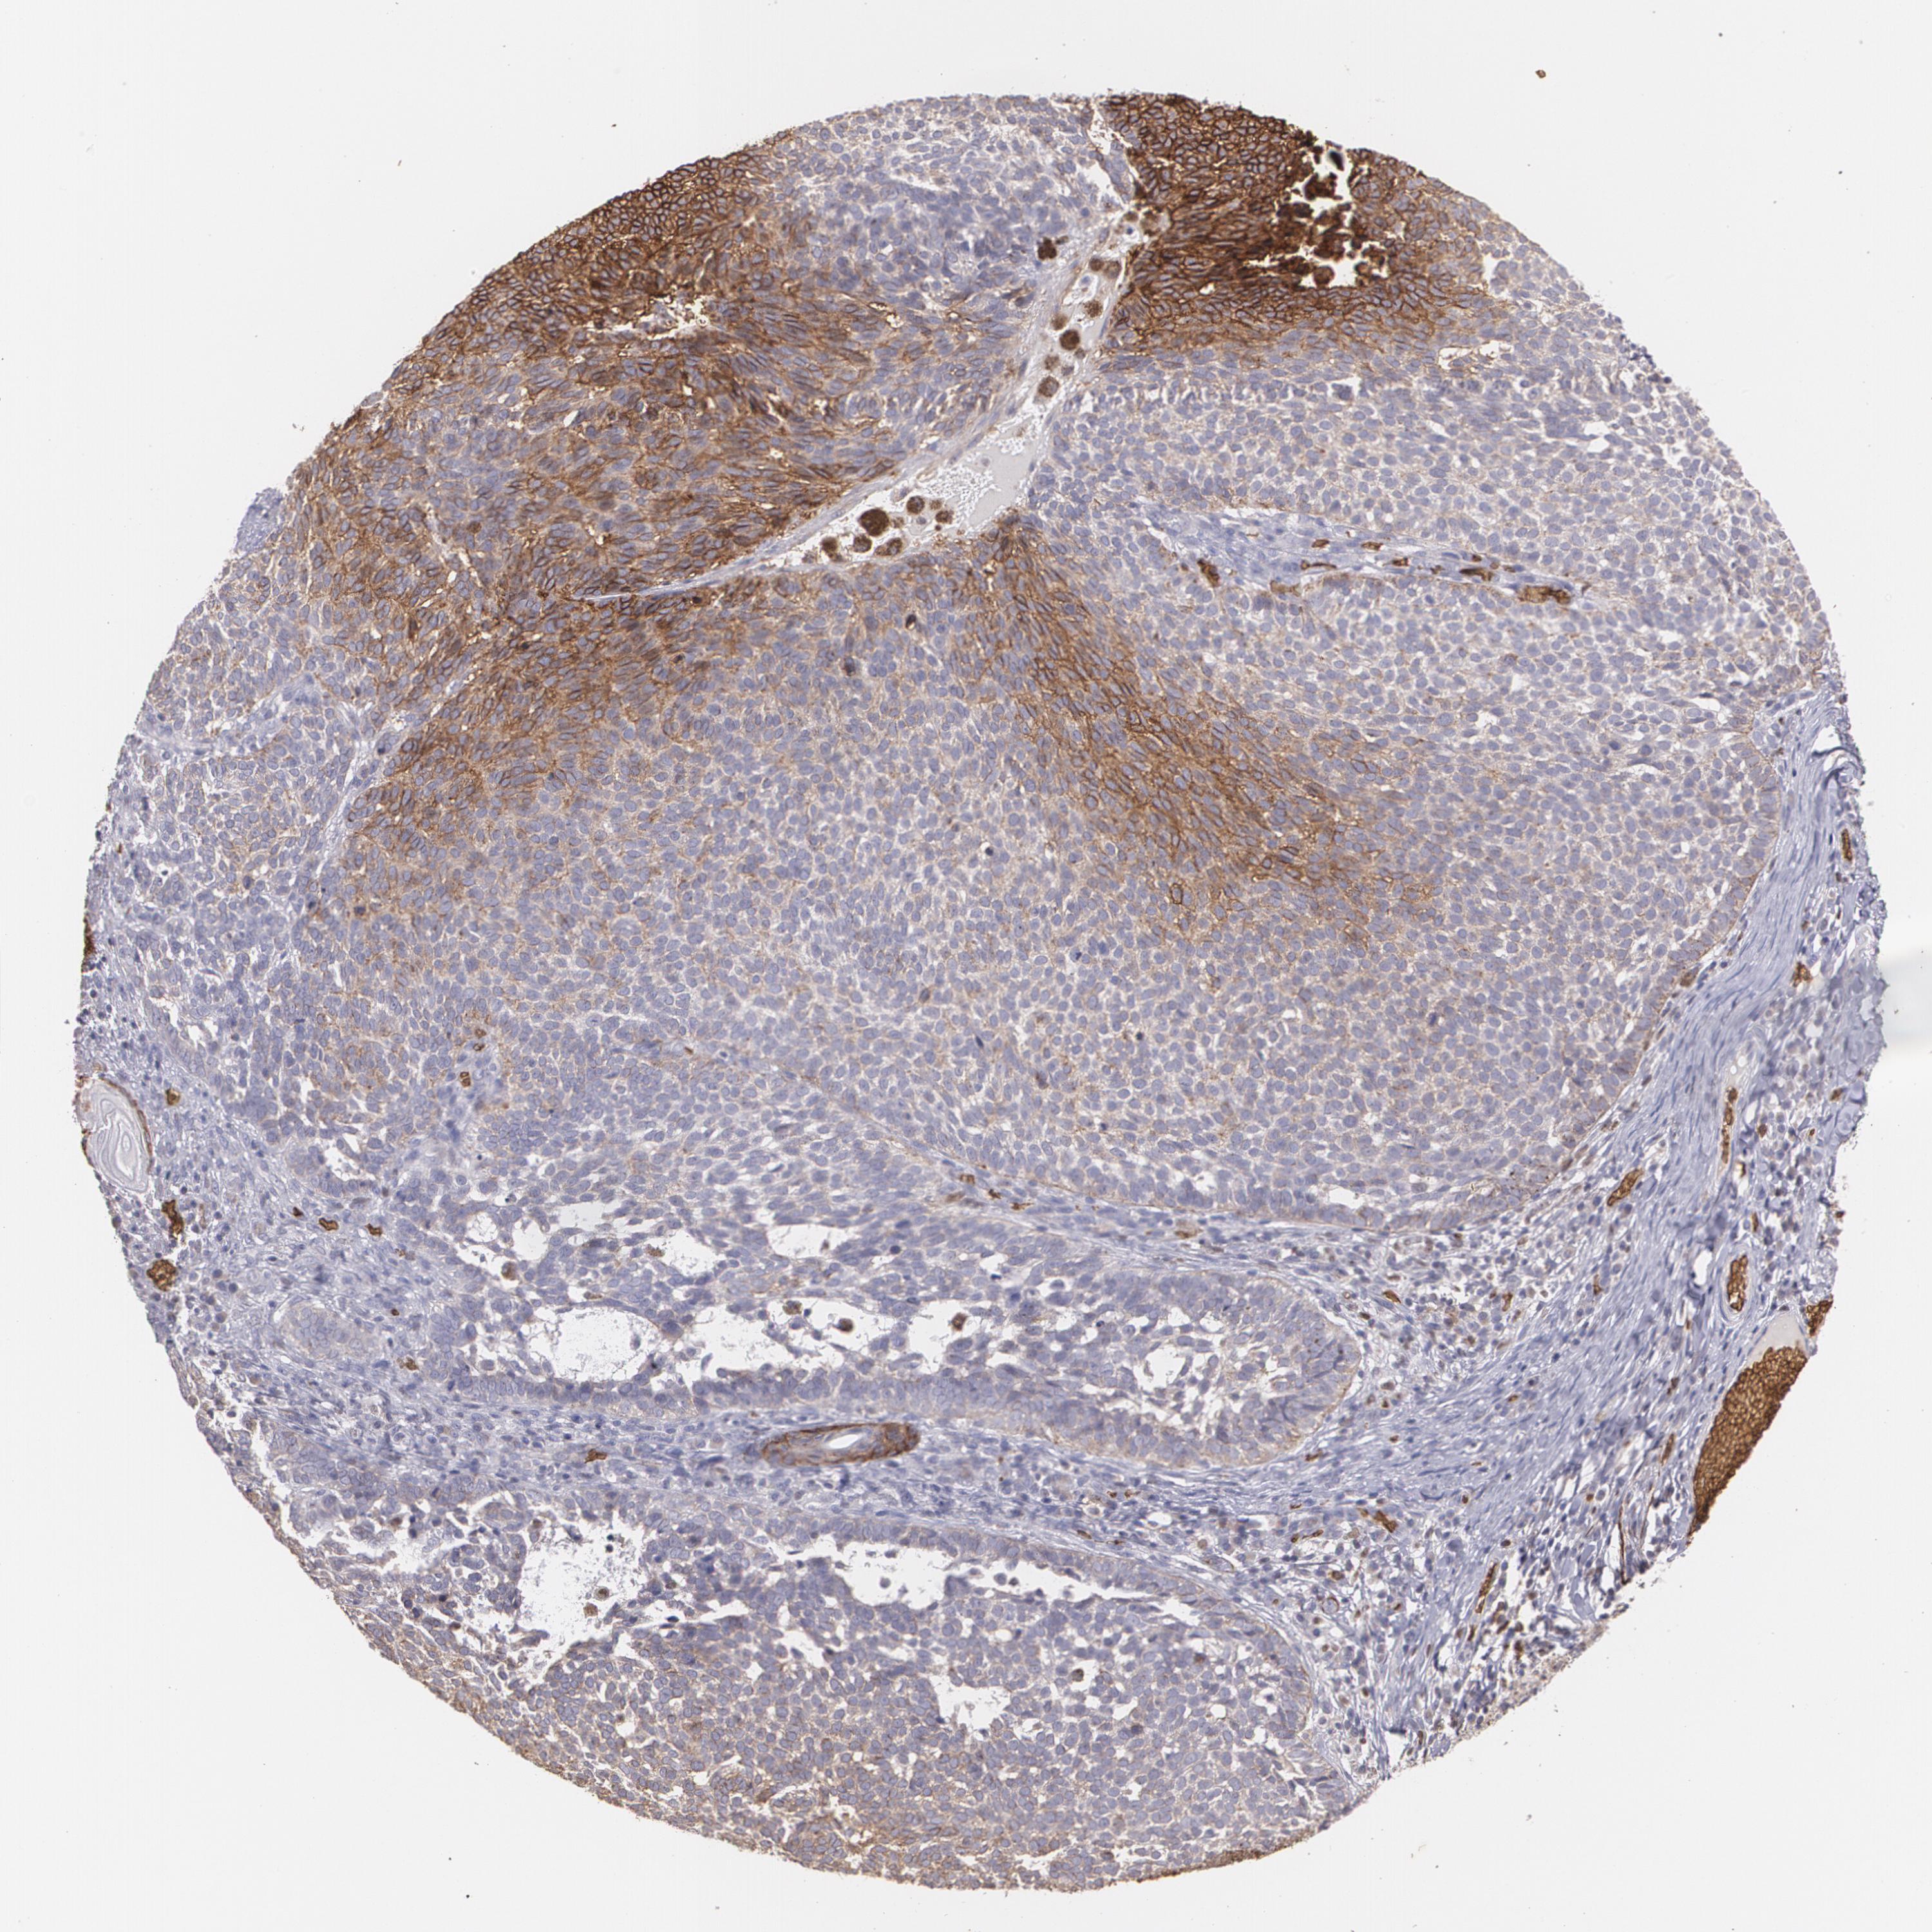

SKIN CANCER - Protein expressioni

A mouse-over function shows sample information and annotation data. Click on an image to view it in a full screen mode. Samples can be filtered based on level of antibody staining by selecting one or several of the following categories: high, medium, low and not detected. The assay and annotation is described here.

Each image is clickable and will lead to virtual microscopy that enables deeper exploration of all samples and also displays staining intensity scores, fraction scores and subcellular localization as well as patient and tissue information for each sample.

Antibody HPA031345

Antibody HPA058494

Antibody CAB002759

Squamous cell carcinoma, metastatic, NOS